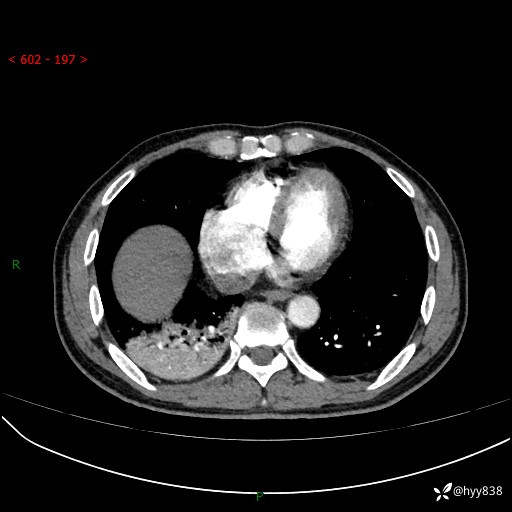

63岁/男,发热5余天。精彩好病例,“大叶性肺炎”,等你来诊---结果公布~

【患者信息】:63岁/男

【主诉】:发热5余天

【现病史及既往史】:患者5余天无明显诱因出现畏寒寒战发热,最高体温39.5℃,发热无明显昼夜规律,伴全身乏力、头晕,无头痛、无咳嗽咳痰、无胸痛咯血、无气短、无腹痛腹泻、无尿频尿急尿痛等不适,于当地市第五人民医院就诊,予以抗感染等治疗(具体不详)后发热无明显好转,1天前查胸部CT提示右下肺感染,为求进一步诊治,门诊以“社区获得性肺炎”收治入院; 起病以来,患者精神、食欲一般,睡眠可,大小便正常,体力体重较前无明显变化。

【检查】:胸部CT增强